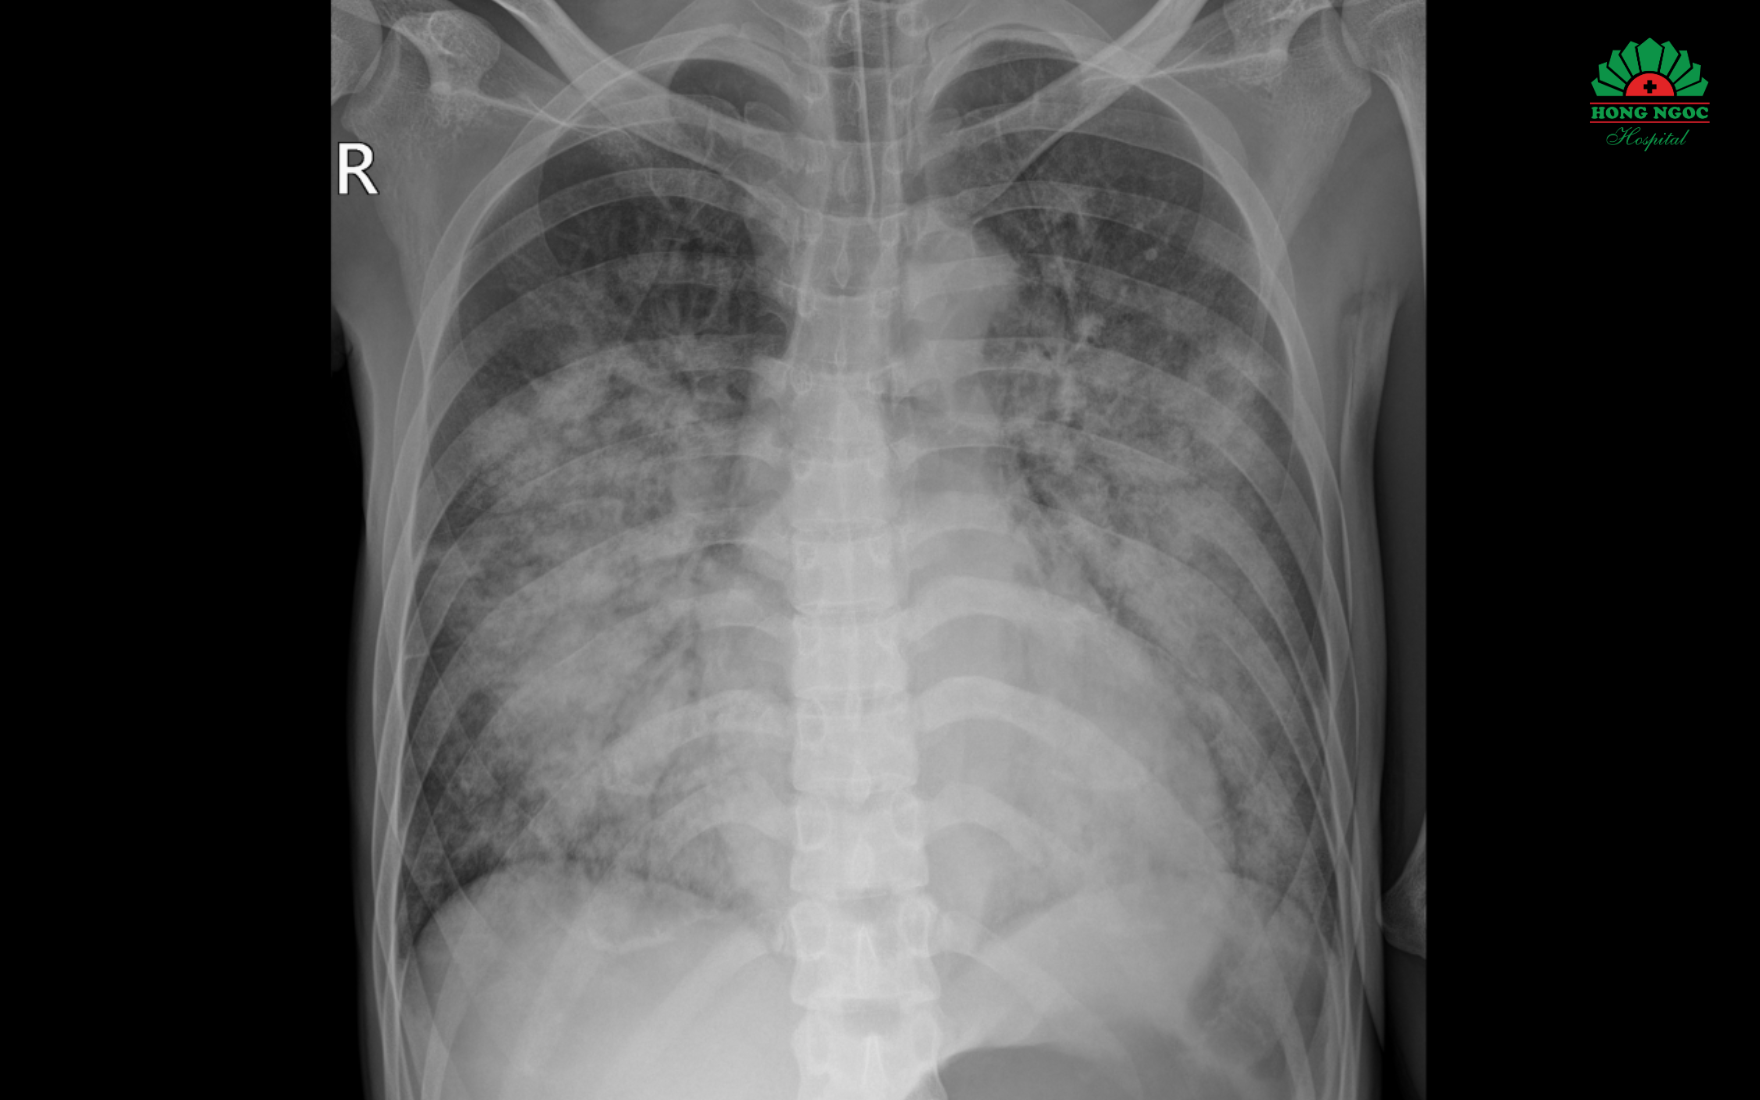

Phim chụp X quang thể hiện tổn thương mờ, lan tỏa 2 phổi của bệnh nhân